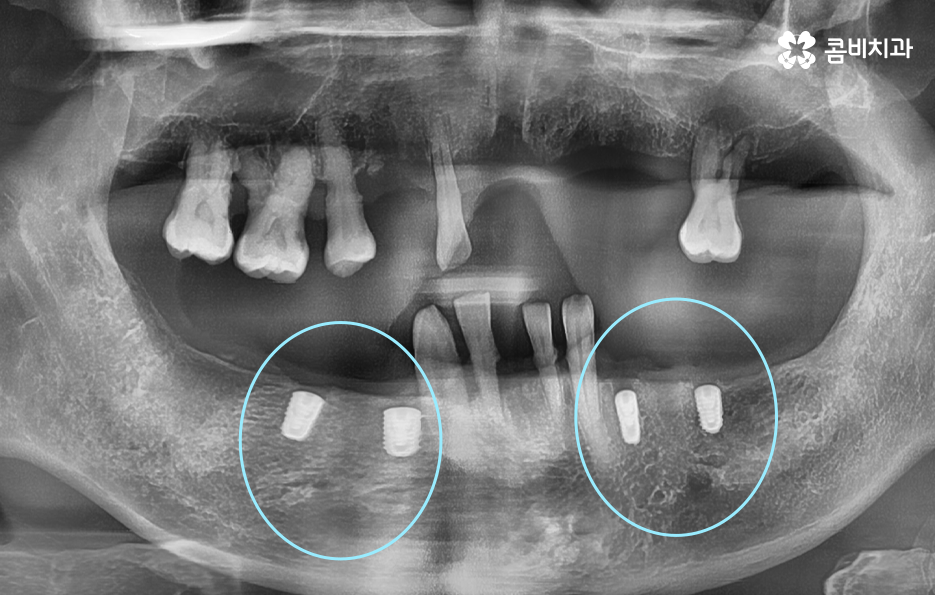

임플란트 브릿지를 활용하여 전체임플란트를 하는 경우 보통 임플란트를 6~8개 정도 식립을 한 후에 임플란트의 머리부분을 연결하여 힘을 분산시키는 방법으로 저작력을 유지시키고 있어요

임플란트 브릿지를 활용하여 전체임플란트 하는 경우에는 환자분의 잇몸 상태에 따라서 다르게 치료 방법이 진행되긴 하겠으나 통상적으로는 치아 역할의 파트 별로 구분하여 보철물을 연결하고 있어요